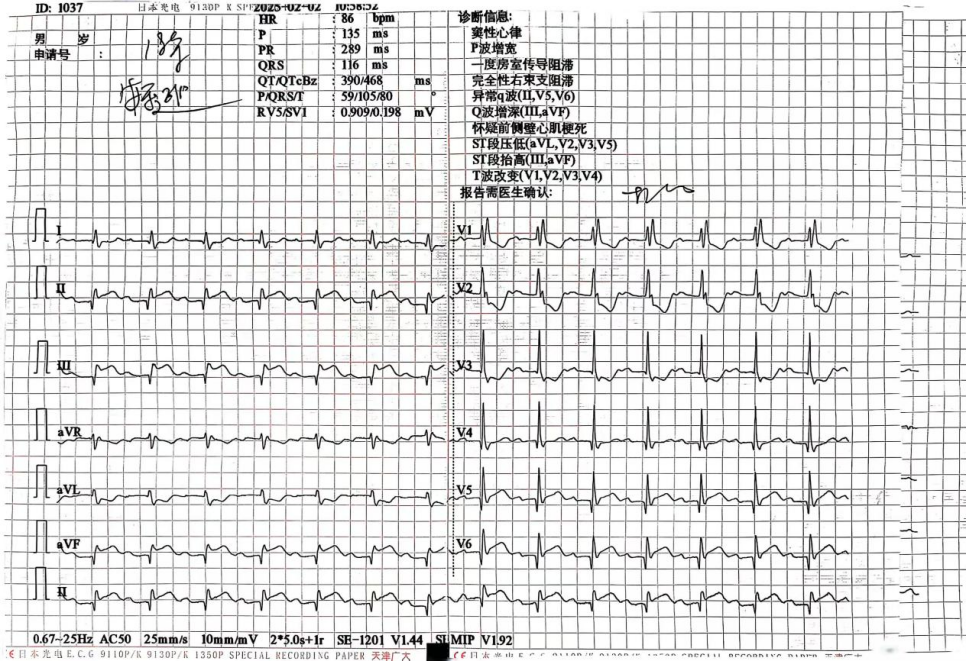

图1、2:术前18导联心电图提示下壁、侧壁、后壁广泛ST段抬高

图3:术前发生三度房室传导阻滞